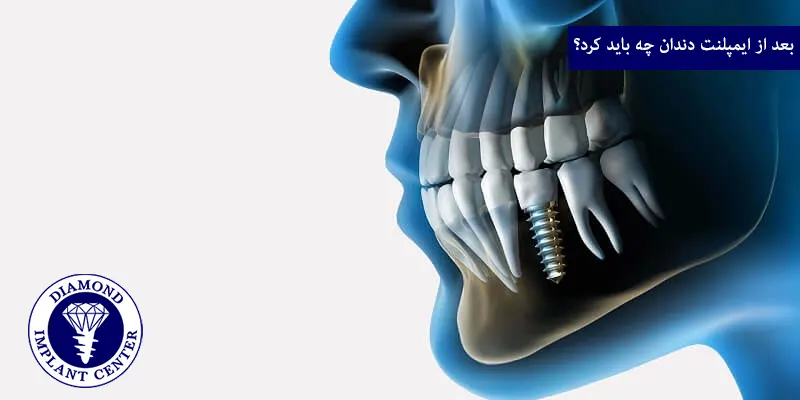

بعد از ایمپلنت دندان چه باید کرد؟

موفقیت بلندمدت ایمپلنت دندان فقط به مراحل ایمپلنت که توسط دندانپزشک انجام میشود بستگی ندارد، بلکه مراقبتهای بعد از ایمپلنت توسط شما نیز نقش بسیار مهمی ایفا میکند.

کنترل درد و تورم

پس از جراحی، داشتن مقداری درد، تورم و کبودی طبیعی است، دندانپزشک معمولا داروهای مسکن و گاهی آنتیبیوتیک تجویز میکند.

رژیم غذایی

در روزهای اول پس از جراحی، فقط غذاهای نرم و خنک مثل سوپ، پوره، ماست، بستنی بخورید و از خوردن غذاهای سفت، ترد، داغ یا تند پرهیز کنید و از نی برای نوشیدن استفاده نکنید.

بهداشت دهان

تمیز نگه داشتن دهان خیلی مهم است، اما در 24 ساعت اول از شستشوی شدید دهان یا تف کردن خودداری کنید.

پرهیز از سیگار و الکل

سیگار کشیدن و مصرف الکل روند بهبودی را به شدت مختل کرده و خطر عفونت و شکست ایمپلنت را بالا میبرد.

فعالیت بدنی

از انجام فعالیتهای بدنی سنگین و ورزش شدید در روزهای اول پس از جراحی خودداری کنید.

مراجعههای منظم

حتما در زمانهای تعیین شده برای کشیدن بخیهها معمولا 1 تا 2 هفته بعد و معاینات بعدی به دندانپزشک مراجعه کنید.